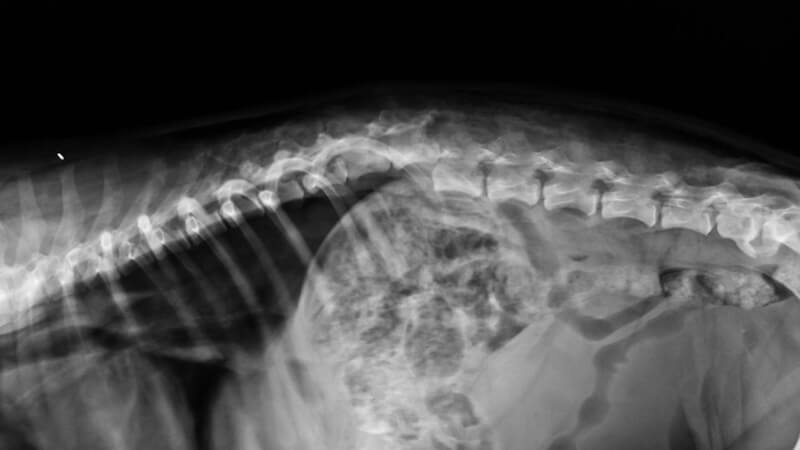

Vertebroplasti, özellikle osteoporoza bağlı gelişen omurga kırıklarının tedavisinde kullanılan minimal invaziv bir cerrahi yöntemdir. Osteoporoz, yaşla birlikte kemik yoğunluğunun azalmasına yol açar ve omurga kemiklerinde çökme kırıklarının en sık sebebidir. Bu kırıklar, şiddetli sırt ve bel ağrılarına, hareket kısıtlılığına ve yaşam kalitesinde ciddi düşüşe yol açabilir. İşte bu noktada vertebroplasti, hem ağrıyı azaltması hem de iyileşme sürecini hızlandırması sayesinde öne çıkmaktadır.

Vertebroplasti işleminde, lokal anestezi veya hafif sedasyon altında ciltte küçük bir kesi açılır. İnce bir iğne yardımıyla kırık omurun içine girilir ve kemik çimentosu (polimetilmetakrilat – PMMA) enjekte edilir. Bu çimento çok kısa sürede sertleşerek kırık bölgeyi stabilize eder. Böylece:

İşlem genellikle 30–60 dakika sürer ve çoğu hasta aynı gün veya ertesi gün taburcu olabilir.